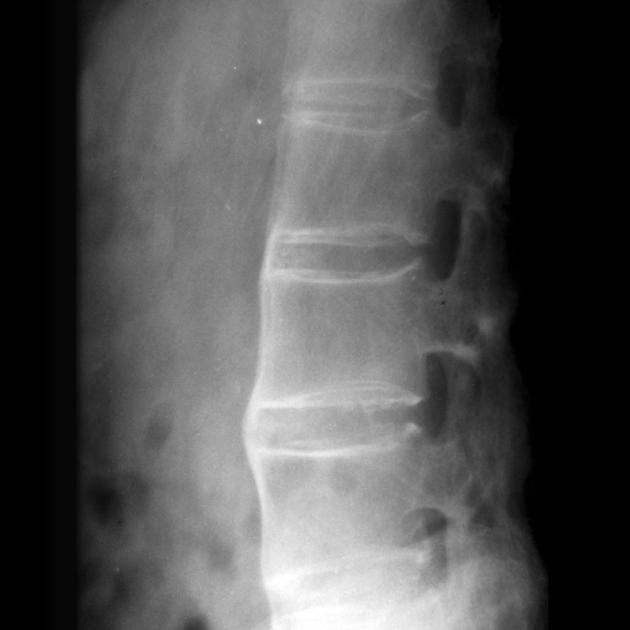

强直性脊柱炎的疾病概述与定义

你是不是经常听到有人说腰疼,但总觉得"年轻人能有什么腰疼"?别急着下结论,有一种疾病专门"欺负"年轻人,它就是强直性脊柱炎。 说起这个病,可能很多人想到的是周...